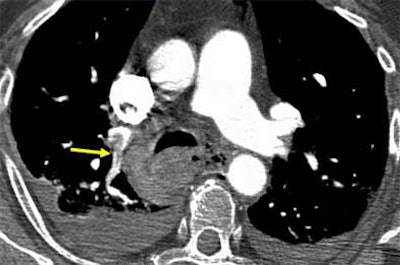

Once a clot is spotted, radiologists must test the theory by asking themselves how the alleged embolus is able to remain immobile, while the pulmonary vasculature goes into high flow "like a toilet flushing," once per second, he said. Is the "embolus" immobile because it's hooked into a vessel? If not, it might be an artifact. True clots should have a visible means of escaping the blood flow. Similarly, he said, a "clot" that appears on just one or two sections on both the right and left sides might be a flow artifact.

| Vascular cutoff sign. Image courtesy of Dr. John Mayo. |